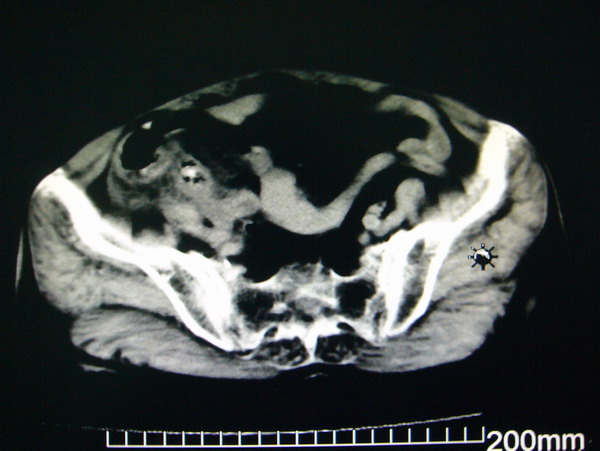

女:83y,转移性右下腹痛2小时,白细胞计数增高。

1.右侧肾盂扩大,肾盏无扩张,考虑:先天性肾盂变异可能性大。

2.胆囊扩张,考虑:胆囊炎。

3.阑尾区域可见以结节样高密度影,结合病史,考虑:阑尾结石,阑尾炎。

右下腹肠系膜增厚,结合病史支持阑尾炎.

右侧壶腹型肾盂可能,建议输路造影或增强

1.右侧肾盂扩大,考虑先天性肾盂变异或肾盂旁囊肿。

2.胆囊扩张,考虑胆囊炎。

3.阑尾区域可见结节样高密度影,结合病史考虑:阑尾结石、阑尾炎。